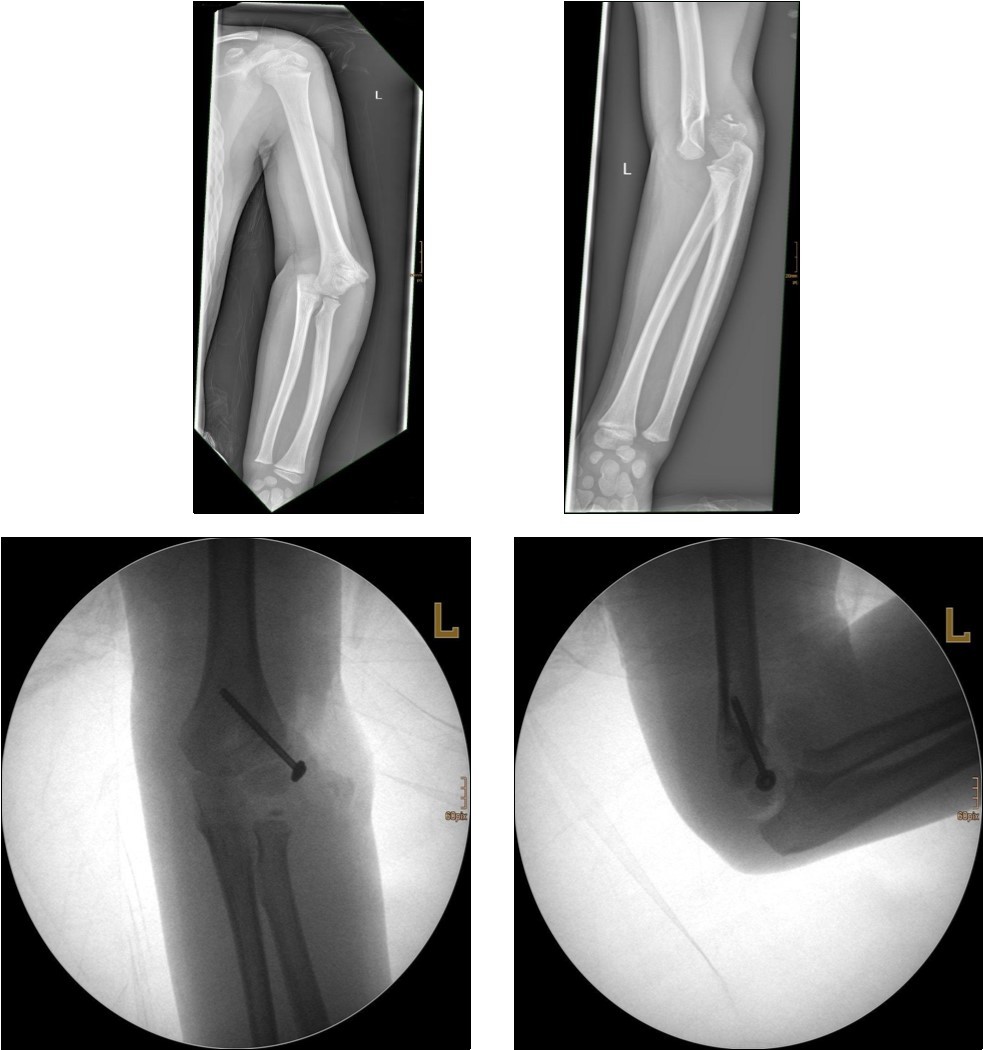

Treatment

Undisplaced fractures are simply immobilized in a cast or posterior splint. As with fractures of the lateral condylar physis union may be slow. In fractures treated promptly, results have been satisfactory. Because there is usually more displacement in older children, the results in this age group are not as satisfactory as those in younger children, who tend to have relatively nondisplaced fractures. For displaced fractures, open reduction with internal fixation is the most often used treatment method.

The fracture fragment can be approached by a posteromedial incision that allows good exposure of both the fracture site and the ulnar nerve. Fixation is easily achieved with smooth K-wires or with screws in older adolescents. Two wires are necessary because of the sagittal rotation forces exerted on the fracture fragment by the common flexor muscles. Figure 4 and Figure 5.

Figure 4.14 year old female patient with a elbow dislocation and a dislocated left epicondyle fracture which was treated by open reduction and osteosynthesis with two divergent Kirschner wires (personal collection)

Figure 5.9 year old female patient with a elbow dislocation and a dislocated right medial condyle fracture which was treated by open reduction and osteosynthesis with a screw (personal collection)